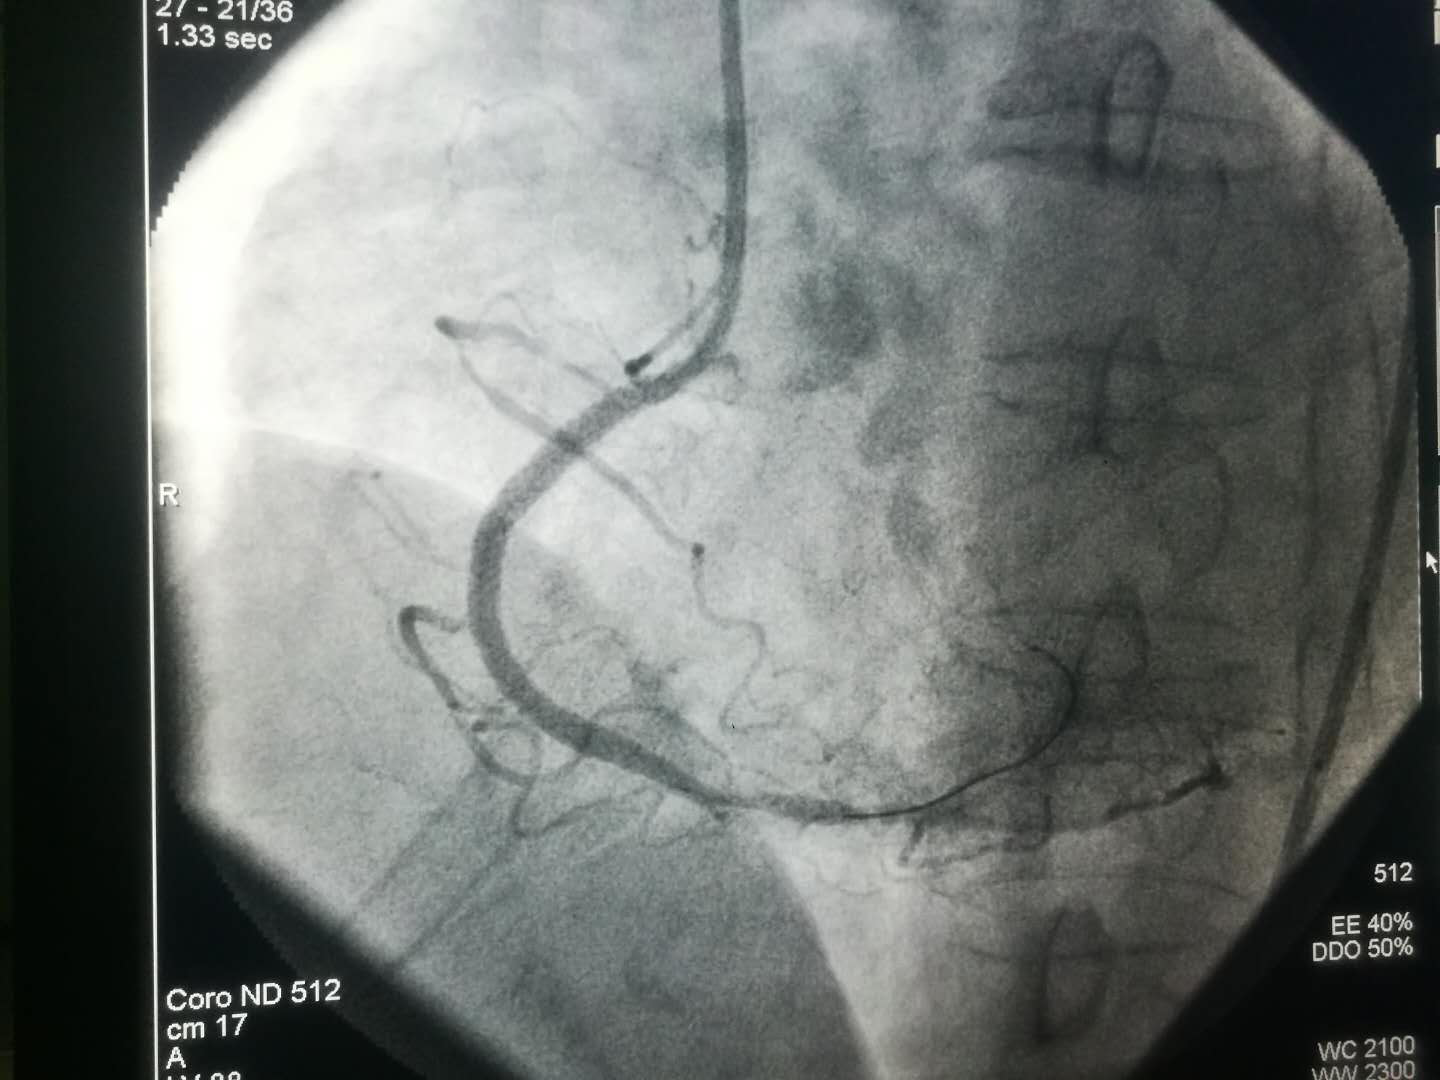

2019新年伊始,文理病区开展了首例冠状动脉造影术及冠状动脉支架植入术。

1月8日上午患者术后在李同华主任的协助下完成文理病区首例冠状动脉造影术加冠状动脉支架植入术。术后患者转入心内四病区监护48小时,1月9日患者平安转回我科继续治疗。整个转诊过程无缝衔接,配合顺畅心血管病成人导航 的各位主任护士长们纷纷表示,只要文理病区需要,术后患者可以转往心血管成人导航 任何一个病区监护。距离无法阻隔我们发展的脚步,无法阻隔我们团结一致为患者服务的信心。